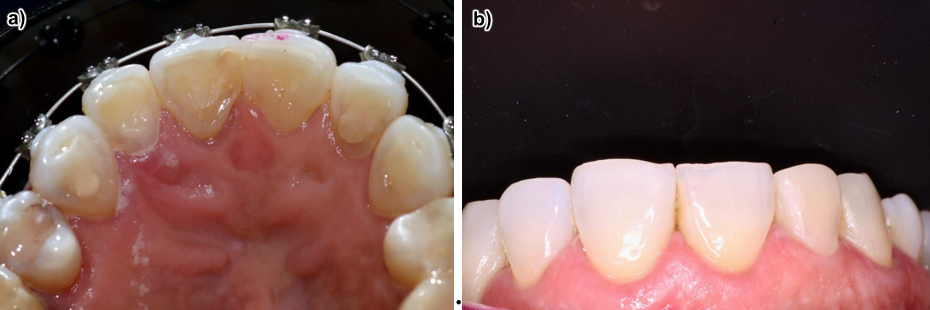

Se realizaron tres secciones del cambio del producto, hasta llegar al objetivo. Finalmente, se realizó la restauración respectiva esperando 10 días, ya que está contraindicado hacerla enseguida por la adhesión (figura 9).

Figura 9. a) Restauración, b) Foto de tratamiento finalizado